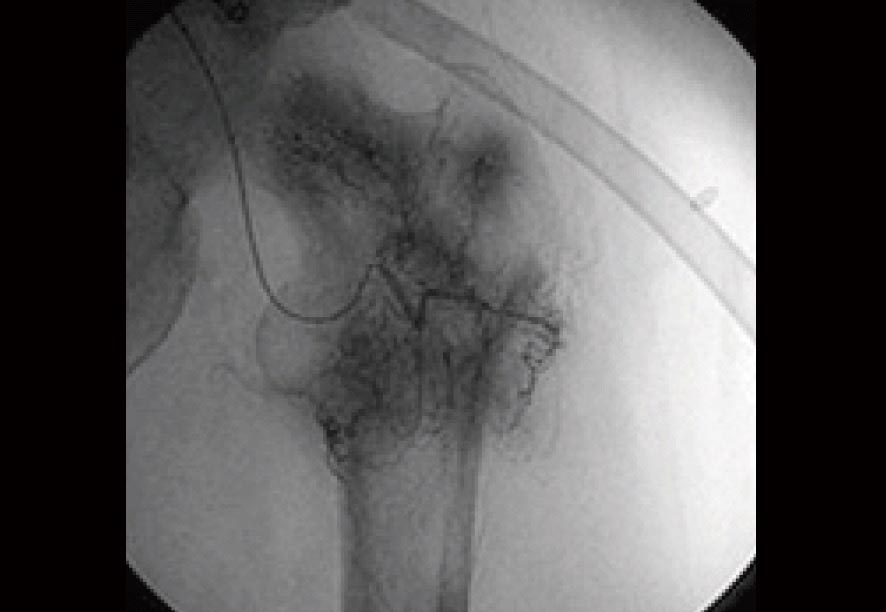

治療前のX線検査結果

参考までに、免疫治療前に実施された血管カテーテルによる骨転移の画像を見てみましょう。

この検査所見によると、左・大腿骨の周囲にはモヤモヤとしたがんの新生血管が密に認められていました(黒い部分)。

当然、この病状にいたっては歩行困難な状況であることは十分に理解できることでしょう。

大腿骨にがんの新生血管が認められたX線画像